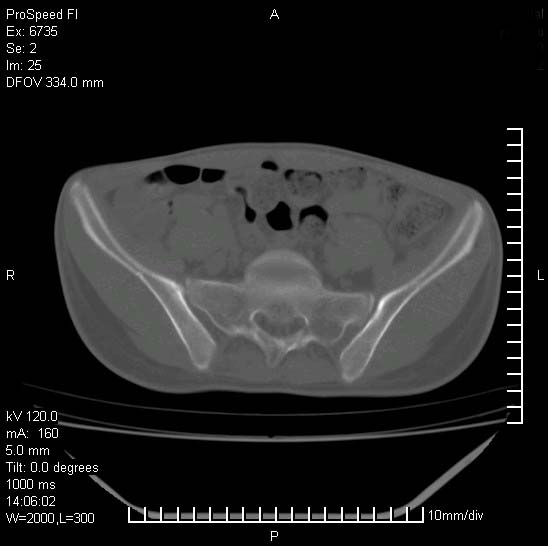

患者自诉胯部疼痛两年余,在当地服用中药,半月前至本院考虑骶髂关节结核,给予抗痨治疗。现发展至右下肢疼痛明显,活动受限,以膝关节处明显,拍膝关节平片无明显异常。

两侧骶骼关节改变,考虑强直性脊炎

右侧骶髂关节也有类似改变,只是较左侧轻,首先考虑强直性脊柱炎,不除外结核,建议作hla-b27检查。

符合强直性脊柱炎表现。